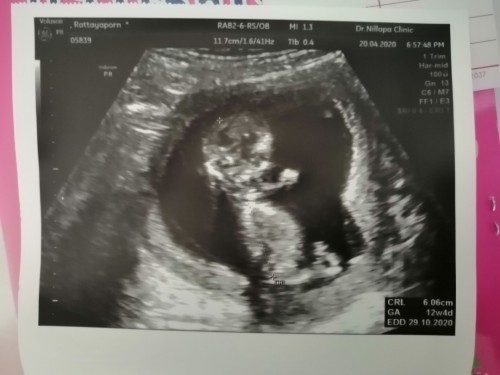

12 วีคค่ะ